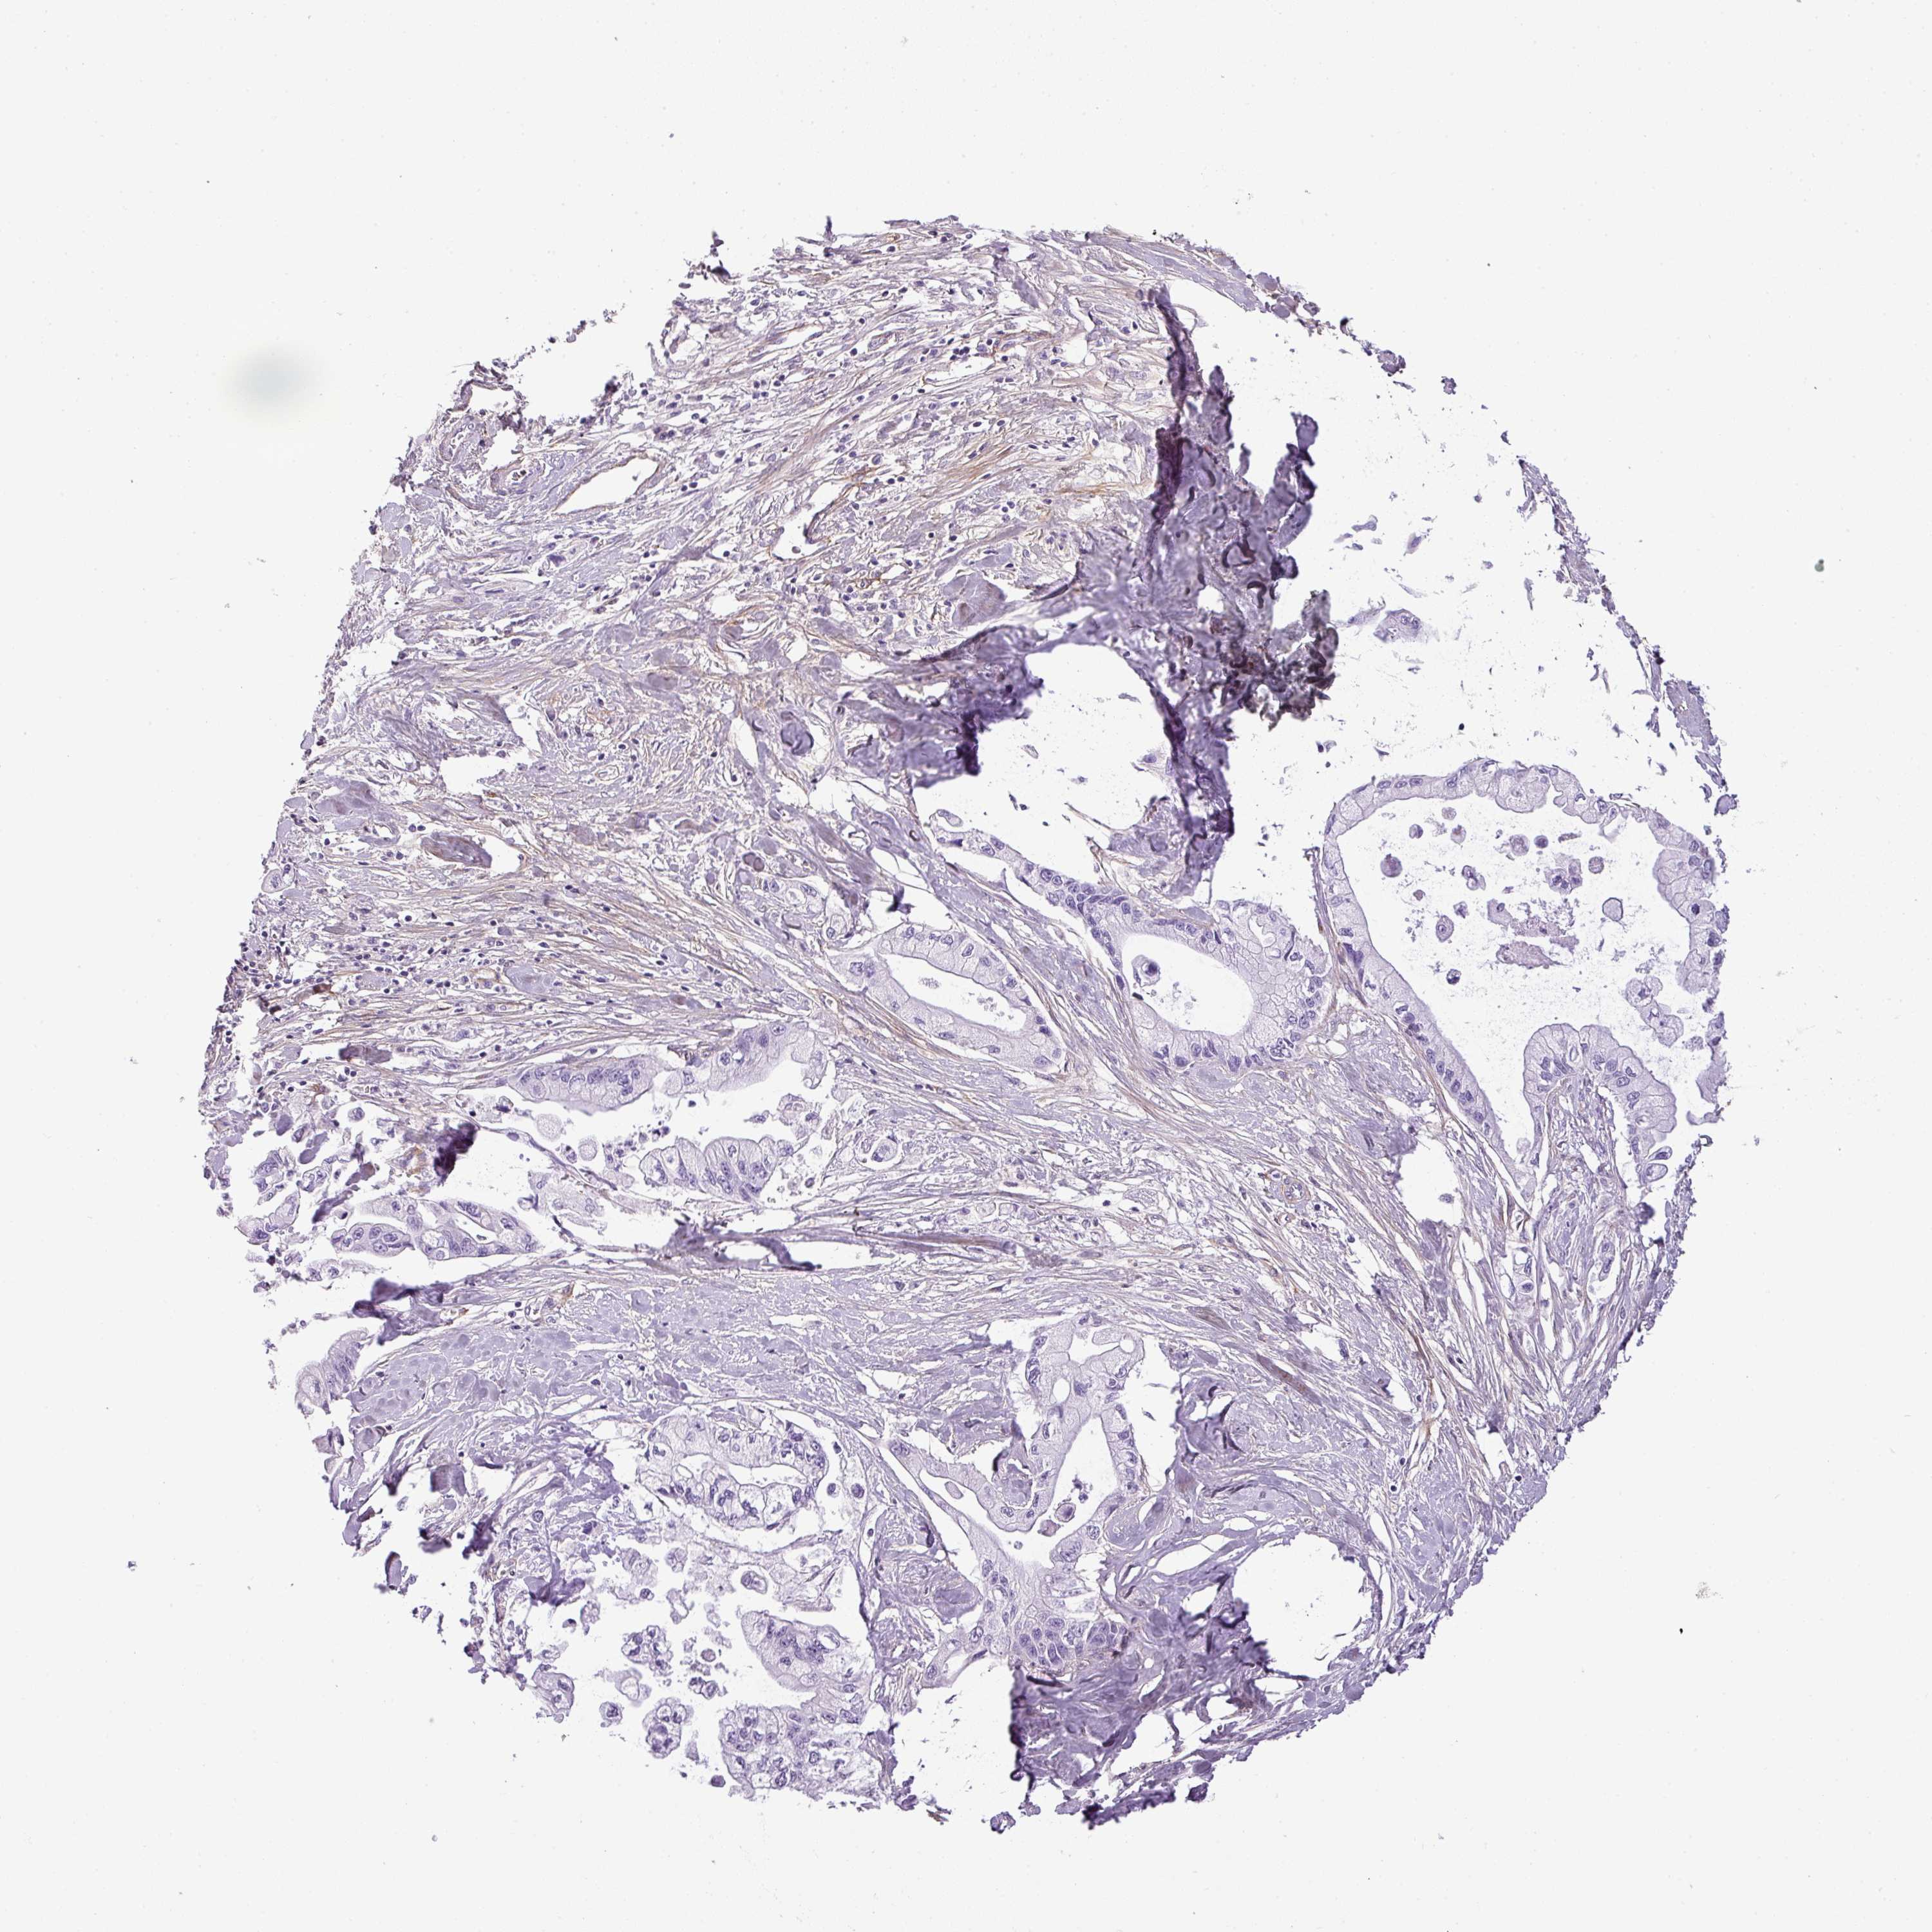

PANCREATIC CANCER - Protein expressioni

A mouse-over function shows sample information and annotation data. Click on an image to view it in a full screen mode. Samples can be filtered based on level of antibody staining by selecting one or several of the following categories: high, medium, low and not detected. The assay and annotation is described here.

Note that samples used for immunohistochemistry by the Human Protein Atlas do not correspond to samples in the TCGA dataset.

Antibody stainingi

Antibody staining in the annotated cell types in the current human tissue is reported as not detected, low, medium, or high, based on conventional immunohistochemistry profiling in selected tissues. This score is based on the combination of the staining intensity and fraction of stained cells.

Each image is clickable and will lead to virtual microscopy that enables deeper exploration of all samples and also displays staining intensity scores, fraction scores and subcellular localization as well as patient and tissue information for each sample.

Antibody HPA047017

Staining

High

Medium

Low

Not detected

Intensity

Strong

Moderate

Weak

Negative

Quantity

>75%

75%-25%

<25%

None

Location

Nuclear

Cytoplasmic/membranous

Cytoplasmic/membranous,nuclear

Adenocarcinoma, NOS